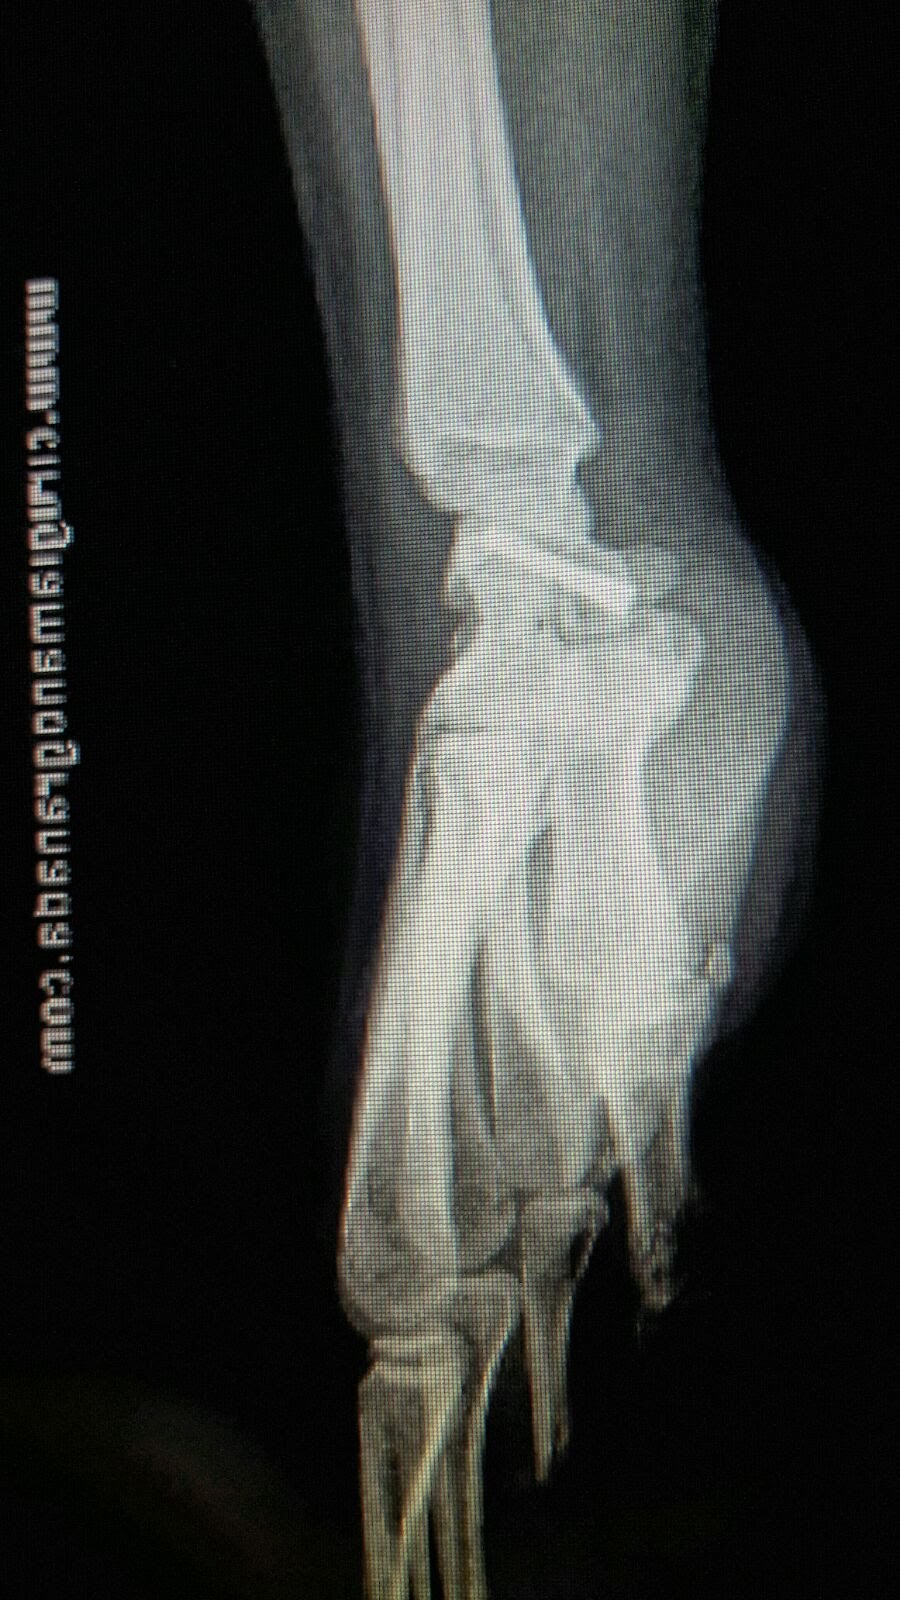

Visión lateral del tornillo